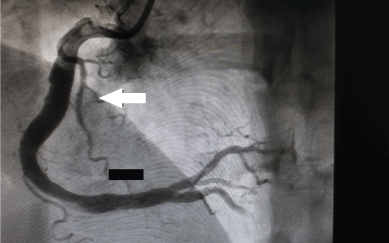

A 44-year-old male with no known risk factors for CAD presented with typical central chest pain. Physical examination was unremarkable. ST and T wave changes were demonstrated in the inferior leads on an ECG. The peak serum troponin T was 39.19 ng/mL (ULN 0.01 ng/mL) the day following presentation. Guideline recommended ACS management was commenced. Coronary angiography was undertaken and revealed CAE in all epicardial vessels but more evident in the RCA (Figure 2A) with TIMI 2 flow in all vessels (Figure 2B). No flow limiting lesions were identified however and accordingly medical management was continued. Mild impairment of left ventricular systolic function was demonstrated on echocardiography with mid inferior hypokinesis. The rest of his hospital stay was unremarkable and he was discharged on day four on guideline recommended medical therapy in addition to dual antiplatelet therapy for twelve months.

Figure 2A: Angiographic findings. Ectasia of the right coronary artery (white arrow). View Figure 2A

Figure 2B: Angiographic findings. Ectasia of left anterior descending (white arrow) and left circumflex coronary arteries (black arrow). View Figure 2B